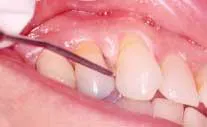

Nicotinic stomatitis, or smoker's palate, is another oral change that is characteristic of smokers. It is characterized by prominent mucous glands with inflammation of the orifices and a diffused erythema, or by a wrinkled, "cobblestone" appearance of the palate often described as a "dried lake bed" effect (See Figure 3). This visual appearance is the result of thickening of the epithelium adjacent to the orifice in response to chronic irritation. The regression of these lesions upon smoking cessation has led many researchers to conclude a cause-and-effect relationship.